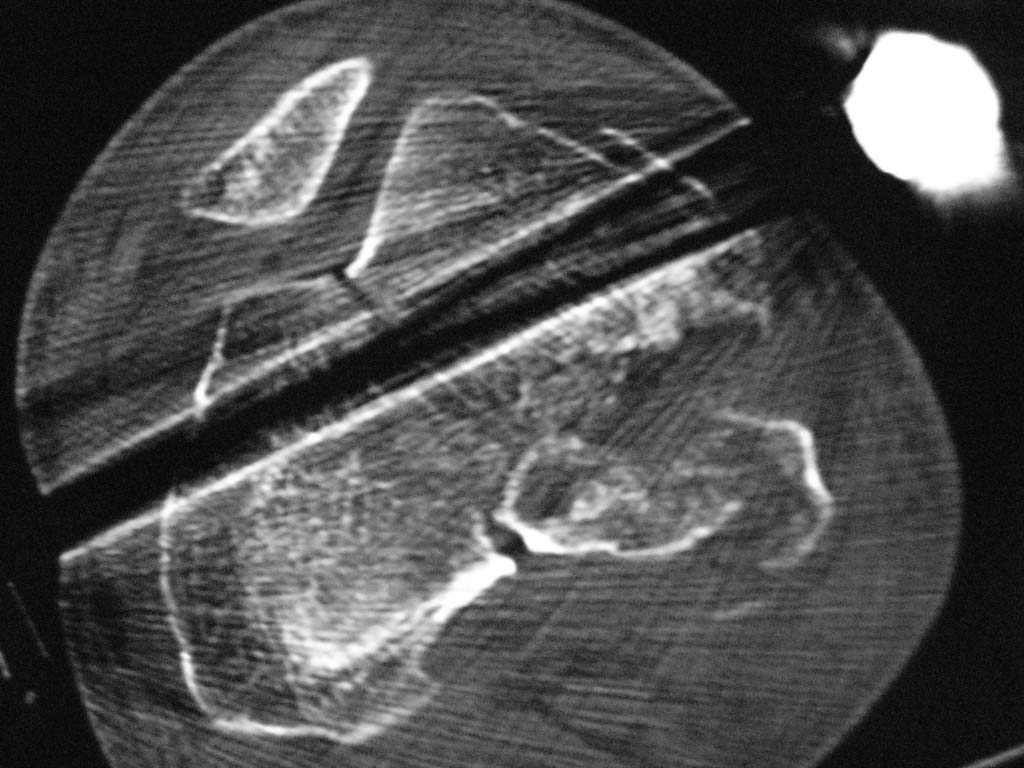

Нужен совет. Открытый перелом в\3 диафиза с оскольчатым переломом дистального метаэпифиза бедра. Закрытый оскольчатый внутрисуставной перелом проксимального отдела большеберцовой кости той же конечности.

При поступлении ПХО ран, скелетное вытяжение. Рана зажила первичным натяжением. Осложнилось правосторонней пневмонией. Предстоит выбрать тактику оперативного лечения и камими имплатнатами.